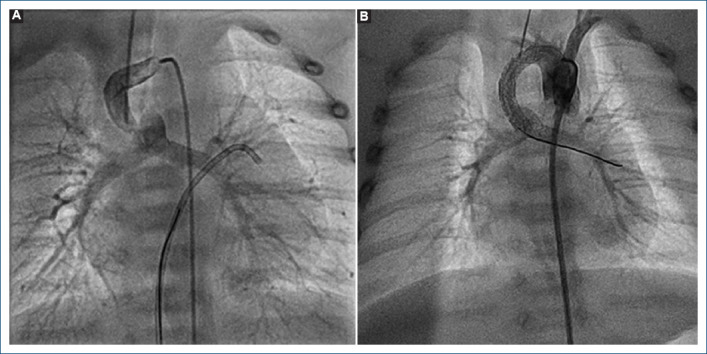

Abstract Image